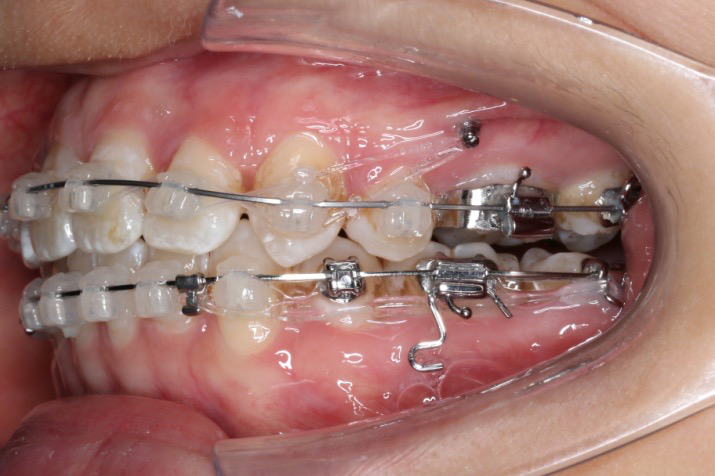

2016.10.31  初戴,0.013cu-niti2017.1.13  上颌加TPA,U56间斜形植入韩国庆北1312-08种植钉,上下0.16cu-niti

2017.02.16  上下0.014*25 cu-niti,50g 拉尖牙远中

2017.04.28

2017.04.28  上0.016*25ss 13、23近远中约5度 v形曲,下0.017*25ss

2017.05.26  磨牙近中倾斜,下颌36、46加power arm

2017.07.25

2017.07.25  上前牙加颈部弹力线